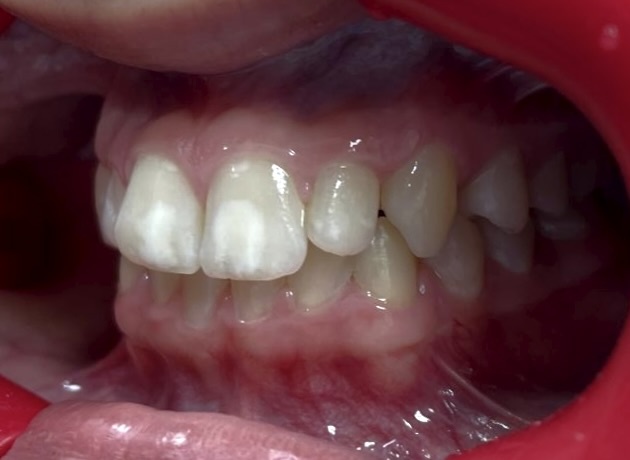

Гипоплазия эмали до исправления прикуса на брекет-системе